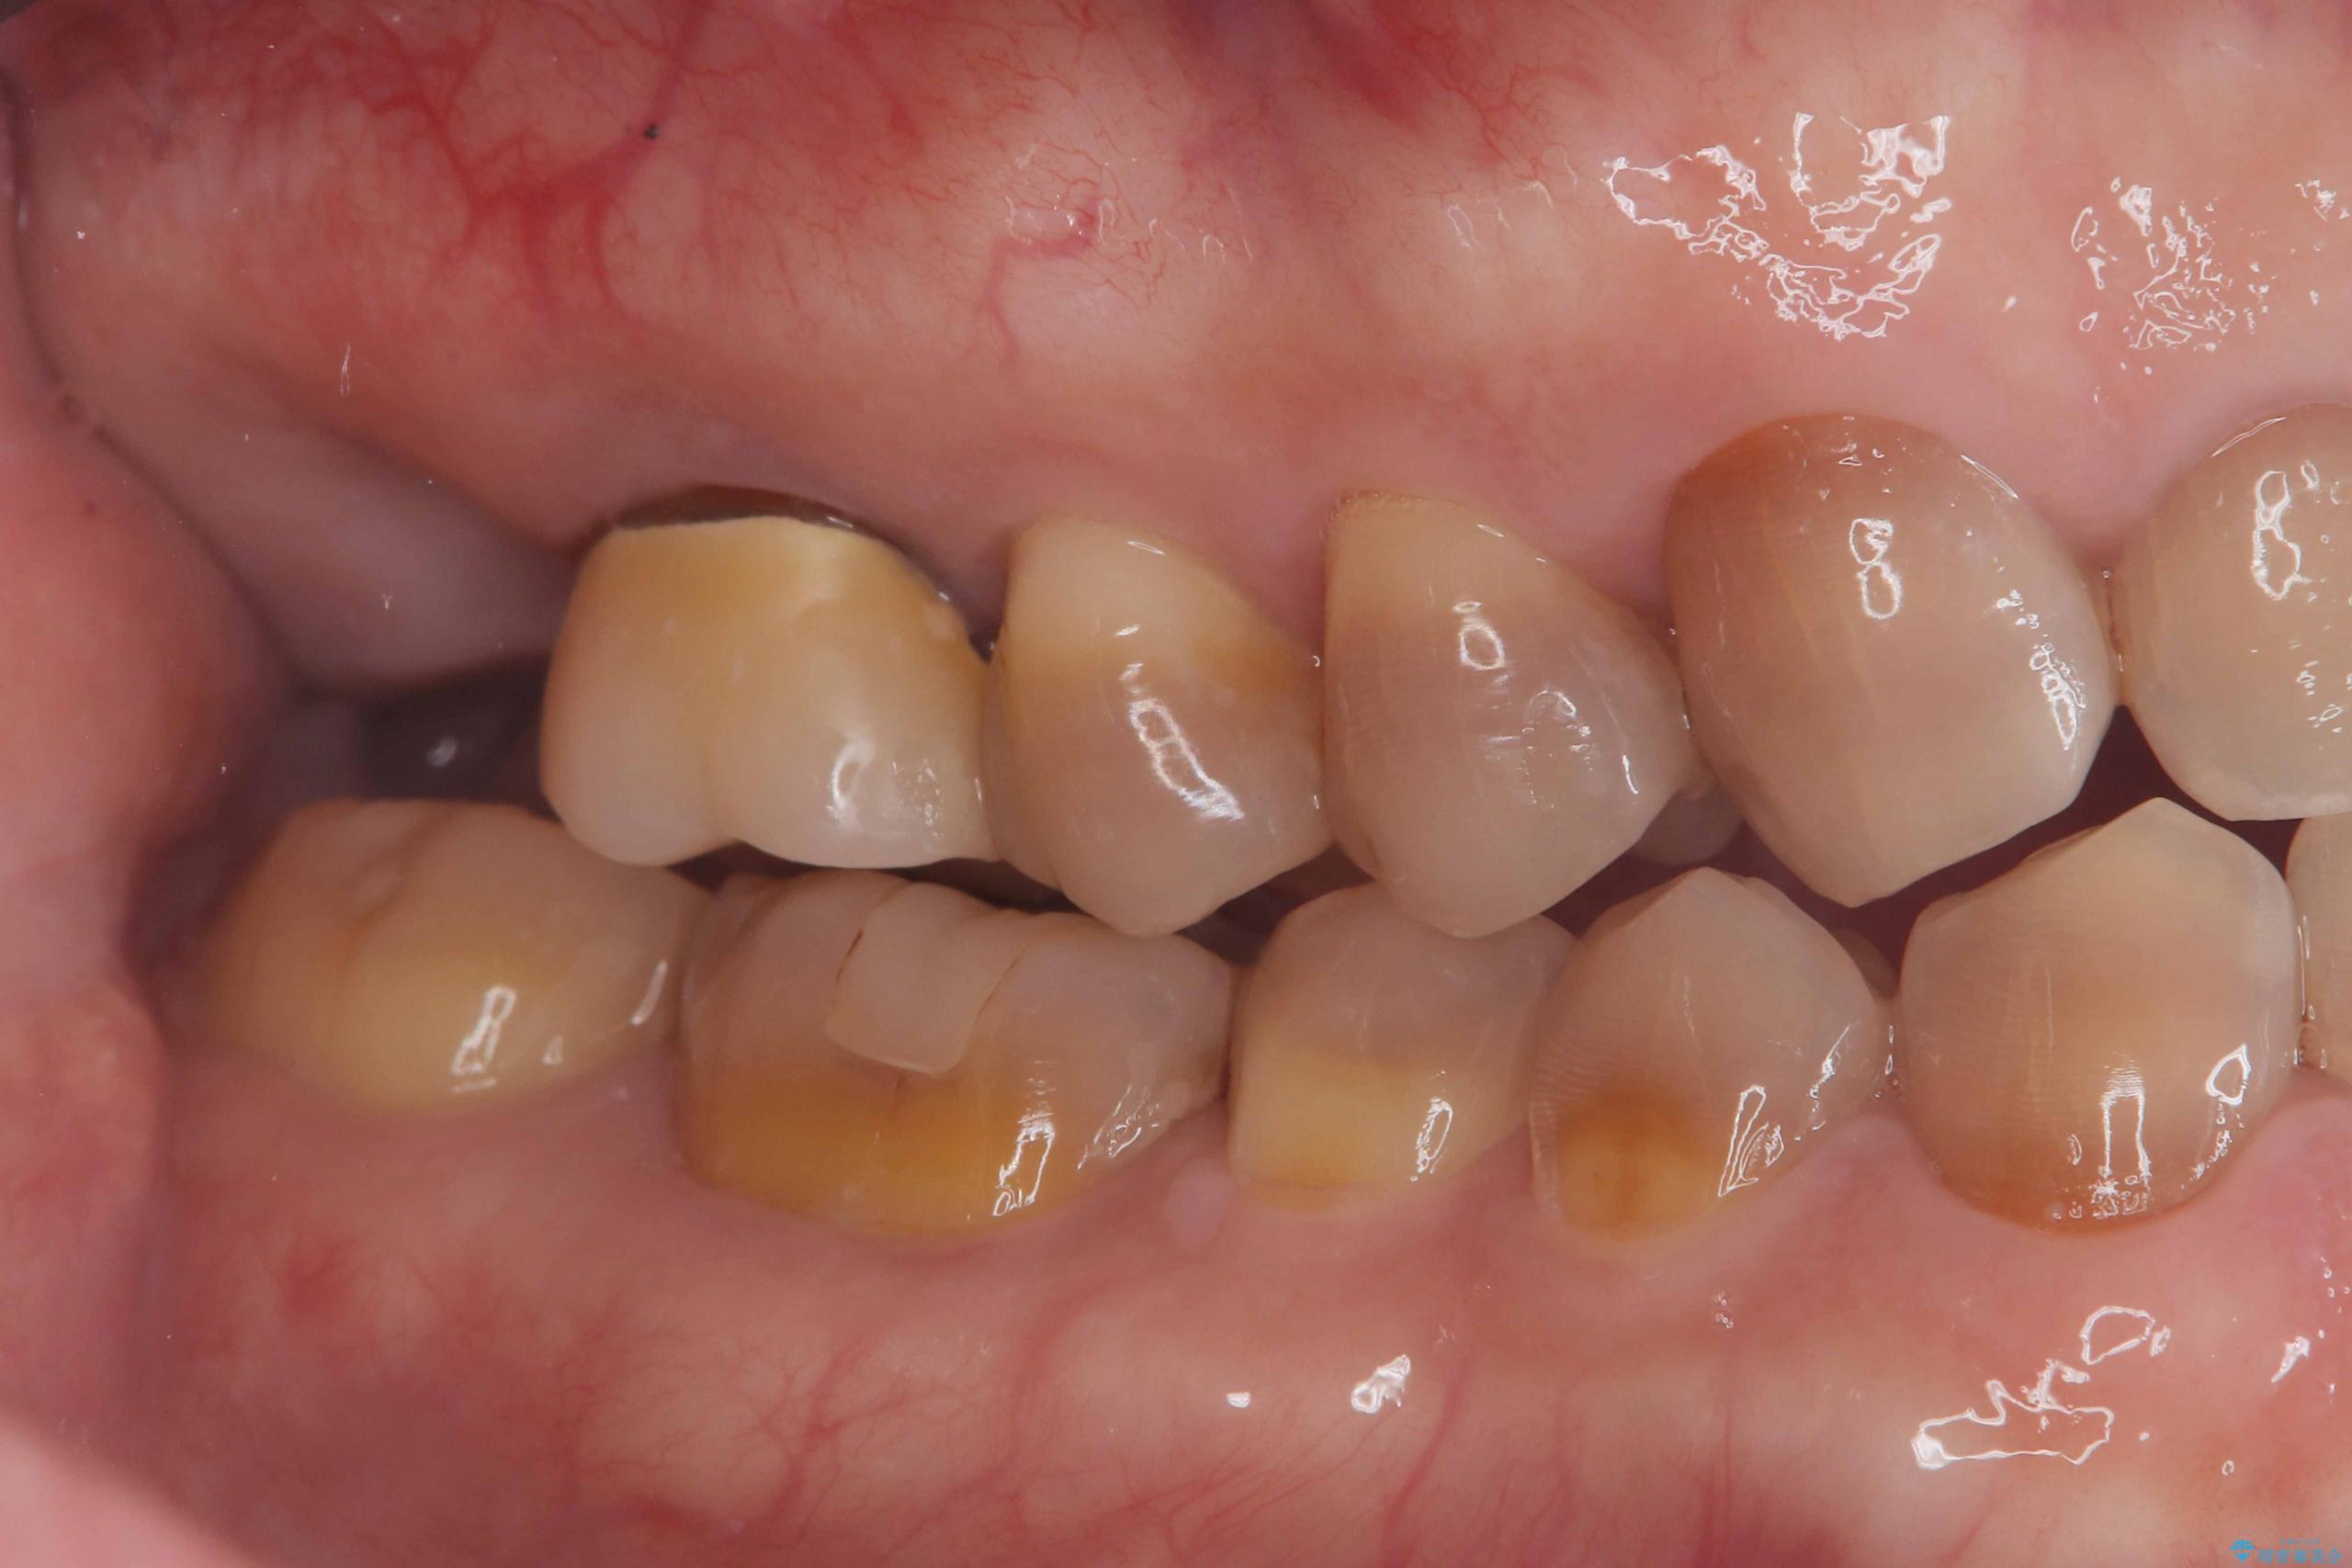

- 治療計画

- 右上7番に瘻孔を認め、根管治療を実施しましたが、瘻孔が再発し治癒が得られなかったため、抜歯のうえインプラントによる補綴治療を行いました。

抜歯と歯根嚢胞の除去を行った後、インプラントで治療しました。治療後は「自分の歯のように咬める」と大変ご満足いただけました。